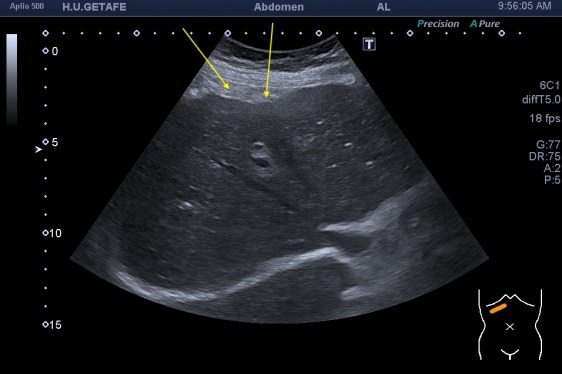

De la imagen 1 a 3 ves un hígado afectado por una cirrosis hepática. En ella vas a ver un tejido anormalmente heterogéneo, parcheado en ocasiones, como con «grumos», a veces muy pequeños, otras veces más grandes. Son los nódulos de regeneración. Cuando las células del tejido hepático se mueren son sustituidas por tejido cicatricial. Puedes ver el borde hepático abombado. Los cambios en la ecogenicidad son variados, te he decimos algunos, no me interesa contarte esto, me interesa que compares la imagen 1,2 y 3 con la imagen 4 y veas patología y normalidad del parénquima hepático. Muchas veces una imagen vale más que mil palabras, lo sé…